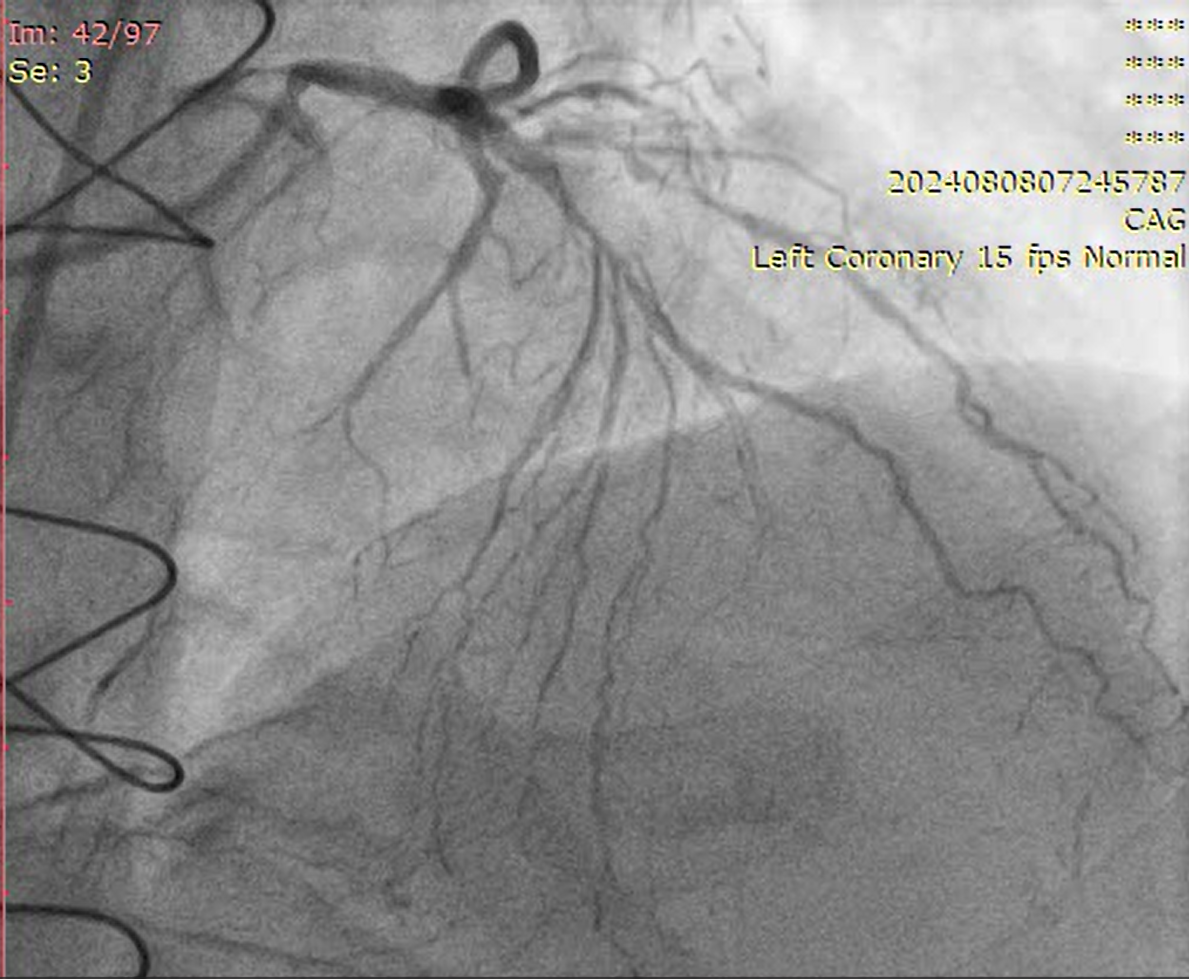

Relevant Catheterization Findings

LMCA: distal mild stenosisLAD: diffusely disease from proximal part with total occlusion in mid part with competitive fillingD1, Ramus, OM1- total occlusionLCX: mild diffuse disease RCA: CTO from proximal part, retrograde filling from LADLIMA to LAD: patentSequential LIMA - RIMA “Y” to OM1 to PDA: occludedSequential RSVG to ramus to PLV branch of RCA- occluded